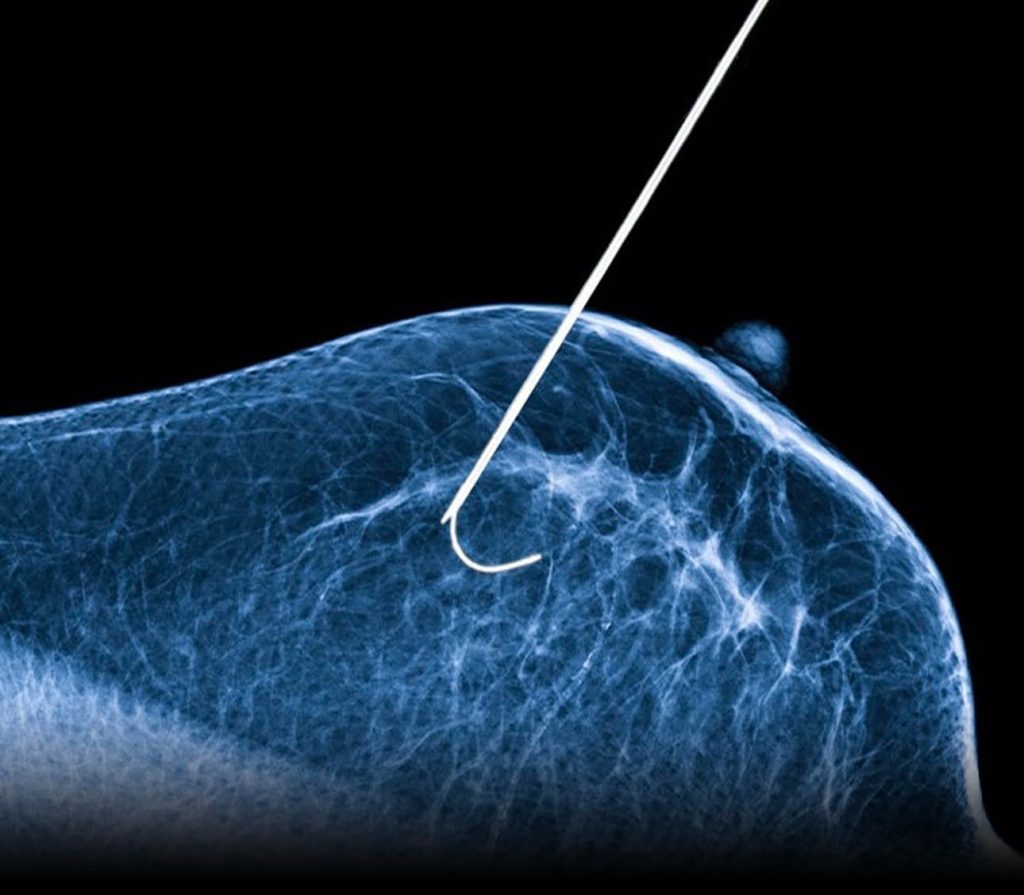

A técnica, chamada de crioablação, foi testada no dia 13 de janeiro na Unidade Diagnóstica do ambulatório de Mastologia do Hospital São Paulo (HSP/HU Unifesp). É a primeira vez que uma instituição pública do país conduz o tratamento. Ele é minimamente invasivo e consiste na aplicação na mama de nitrogênio líquido para gerar temperaturas extremamente baixas e congelar e destruir as células cancerígenas.

“Inserimos, por meio de uma agulha, o nitrogênio líquido a uma temperatura de cerca de 140 graus negativos na região afetada, o que forma uma esfera de gelo, destruindo o tumor.

A incisão deixada pela agulha é igual ou até menor à própria biópsia realizada pela paciente”, disse Afonso Nazário, professor da Unifesp responsável pelos testes com a técnica.